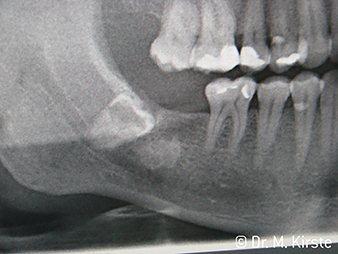

W&H Röntgen

res. 6:

Örnek vaka: 48 numaralı gömük diş ...

W&H Örnek vaka

Fig. 7:

... yeni angldruva kullanılarak düzgünce kaldırıldı.